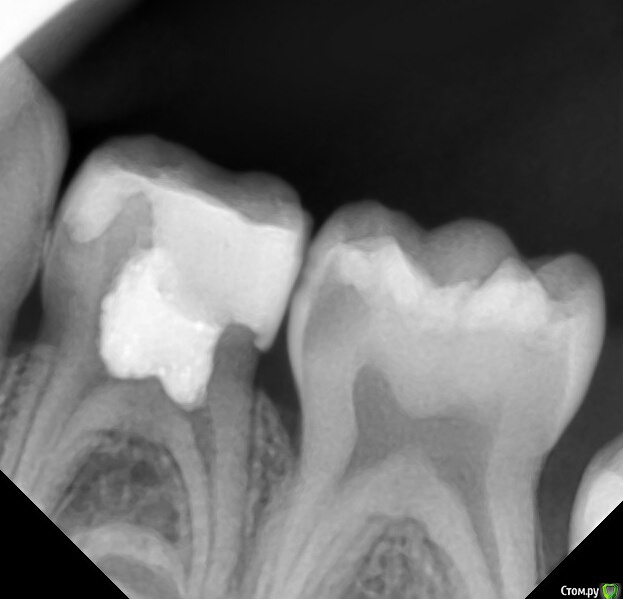

CRAZYDUCK Опубликовано 16 апреля, 2016 Поделиться Опубликовано 16 апреля, 2016 Я вот отказался от пульпотека, у меня были осложнения в виде полной резорбции корней, при условии герметичности. Пульпотек это формальдегид, соответсвенно он мумифицирует, а мумифицировать можно только мертвую ткань, а пульпа у нас живая. Я читал что полиоксиметилен(полиформальдегид), который входит в состав порошка коагулирует альбумины, тем самым вызывает поверхностную девитализацию, но на какую глубину он девитализирует? и до куда проникает формалин? как вообще это все работает? имхо он просто убивает зону роста, с последующей резорбцией корней, я пасс.Каждому свое ,crown, я не могу о пульпотеке плохо сказать,но несколько месяцев им не работаю ,перешла на рутдент быстротвердеющий (мта ),но перешла по след причинам -пульпотек очень резко пахнет (до слез в глазах ),и хочется что-то новое пробовать. Но работала пульпотеком почти 6 лет и результаты хорошие ,патологической резорбции не наблюдала,были осложнения очень давно ,но в тех случаях ,в которых реставрация большой полости сделана витремером ,он скалывался по контакту и тд.Прикрепляю только два снимка с пульпотеком ,наблюдения больше года ,снимки делала для диагностики "скрытого " кариеса на 5 ,поэтому корни не полностью у 4 . Но неплохих снимков с пульпотеком очень много Если несложно ,выложите с мта .интересно посмотреть . 2 Ссылка на комментарий